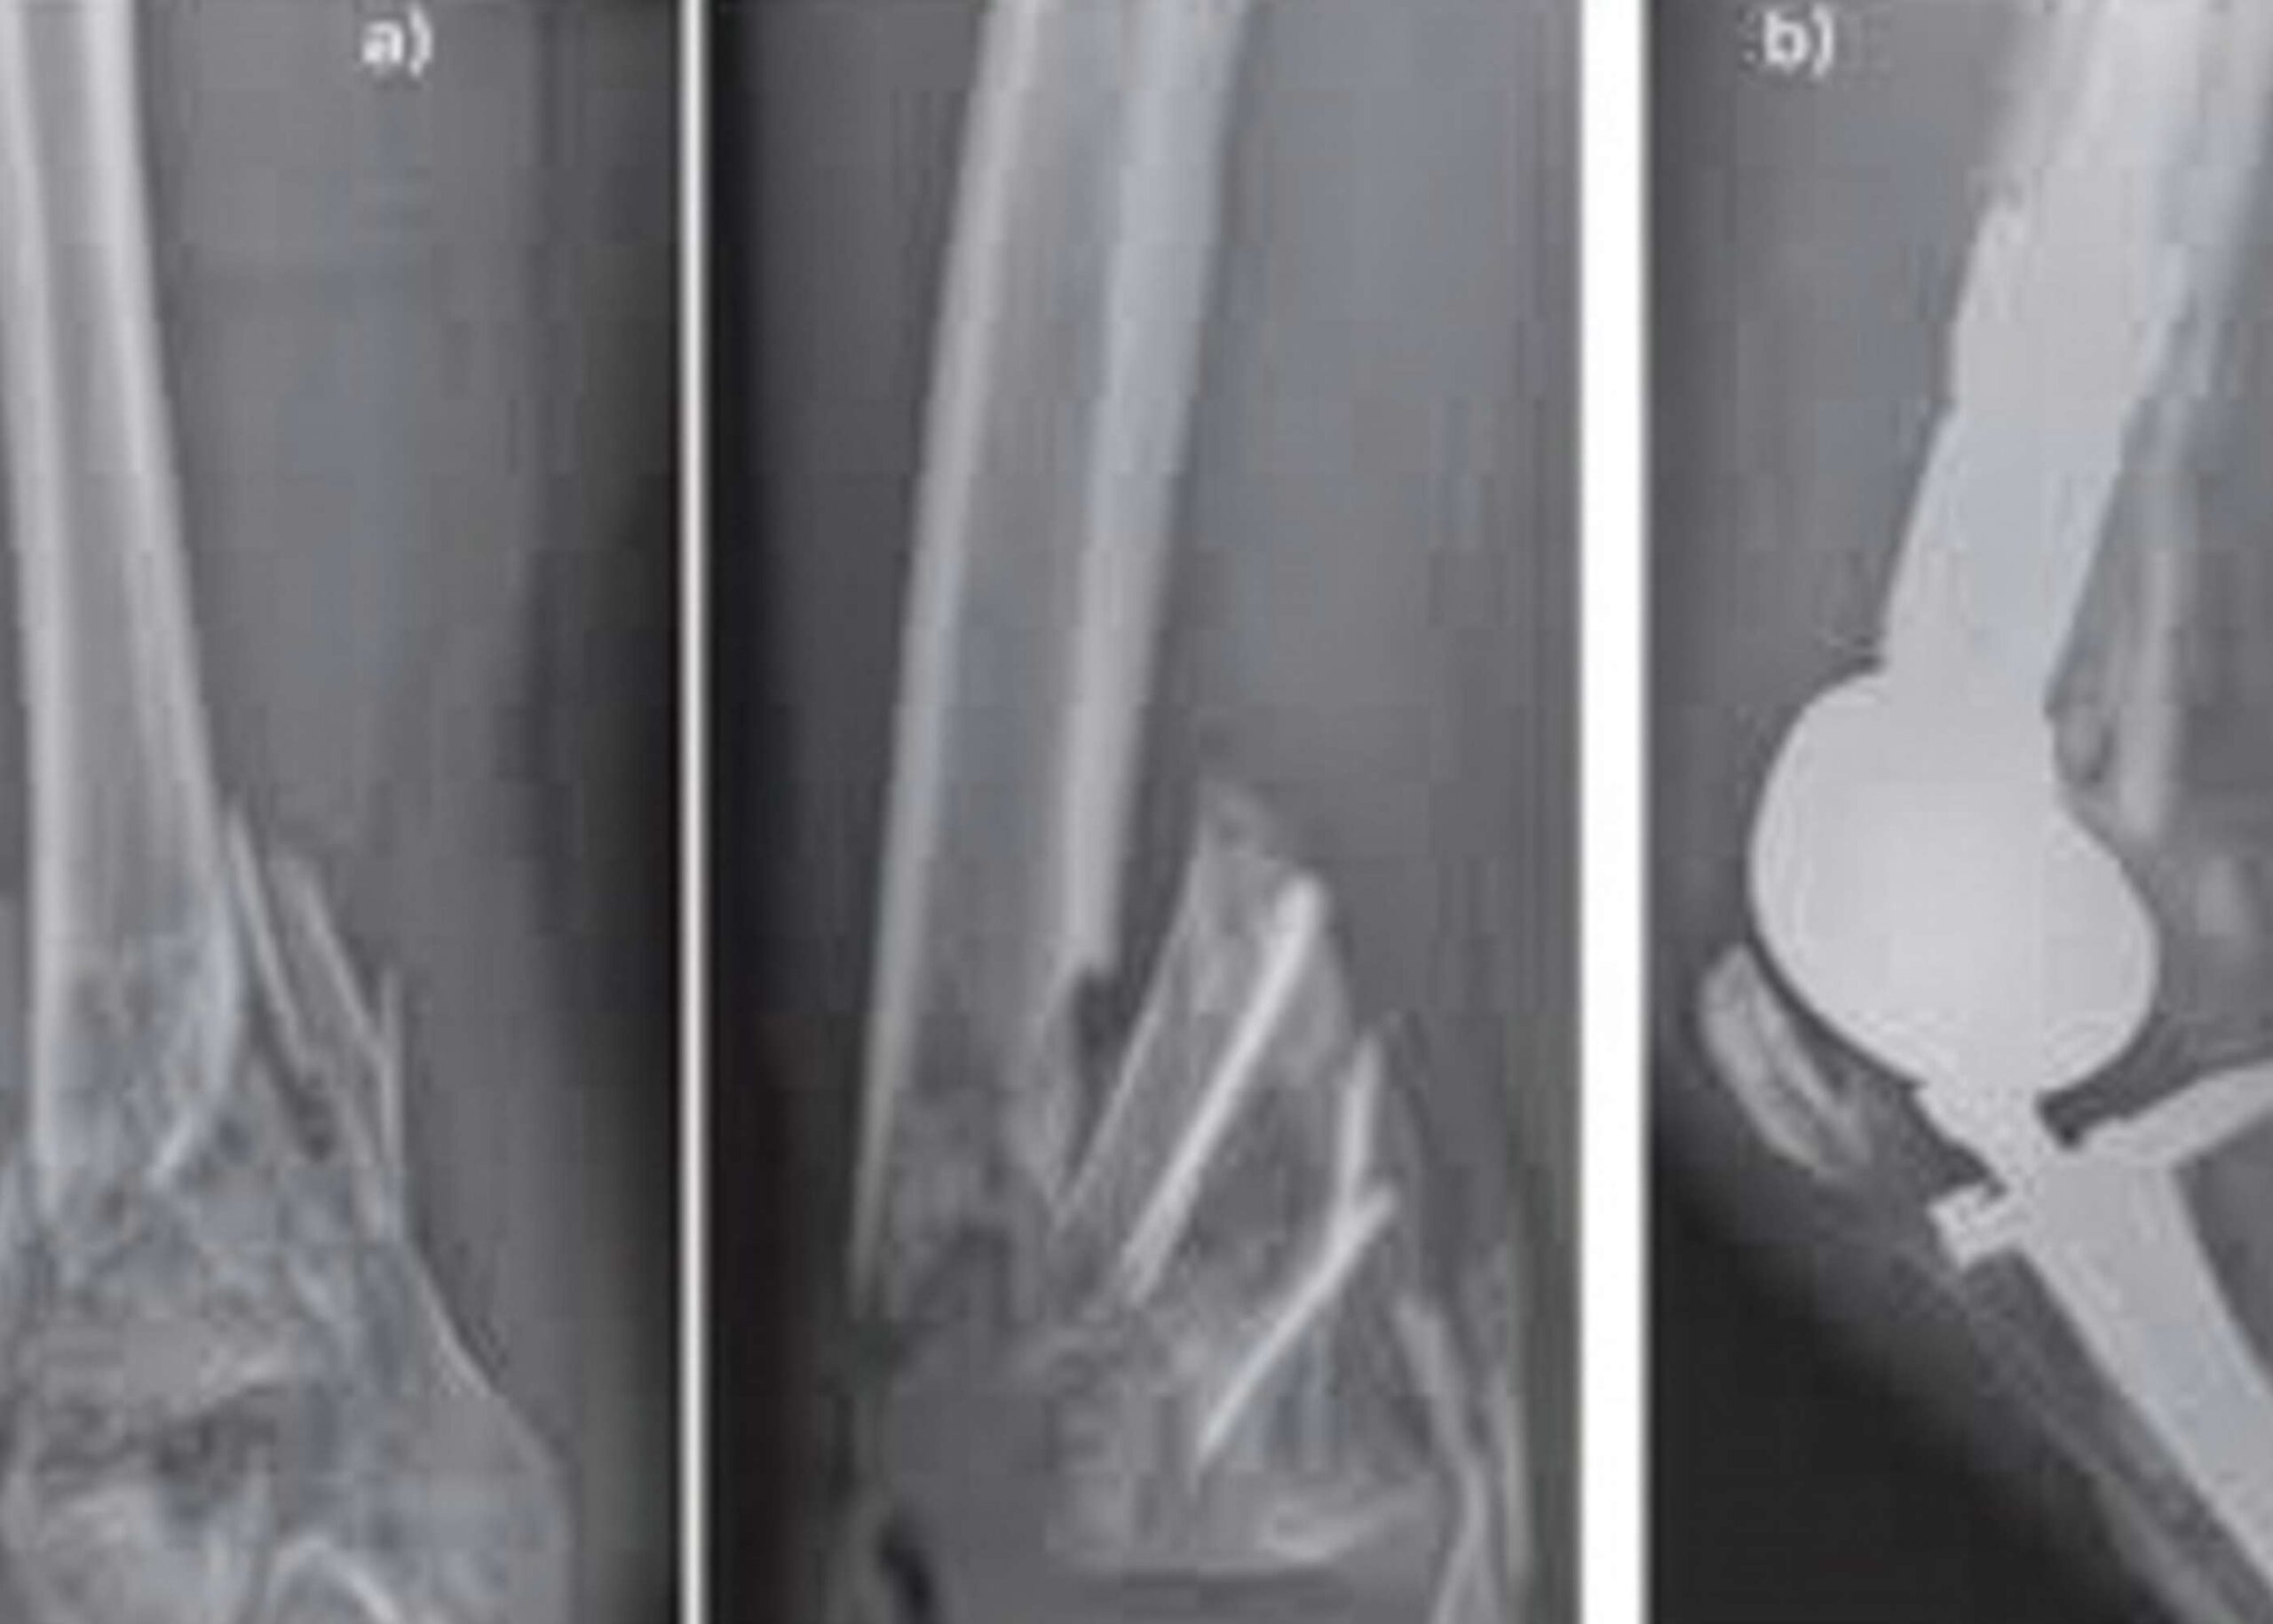

It is an Orthopaedics hospital providing comprehensive care related to musculoskeletal system which includes